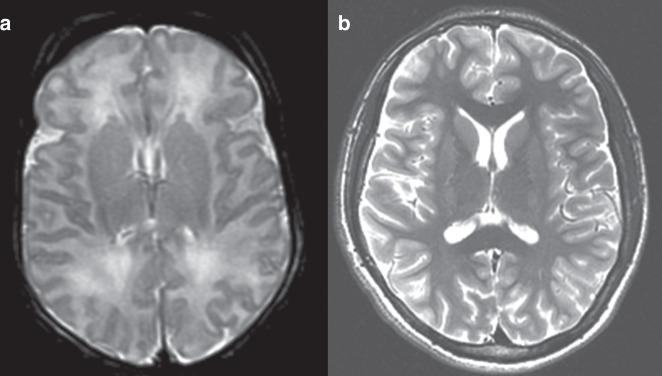

We previously reported that increasing severity of watershed (WS) injury in neonatal magnetic resonance imaging (MRI) is associated with worse language outcomes in early childhood. In the present study, we investigated the relationship between neonatal injury patterns and cognitive profile in adolescents with neonatal encephalopathy.

Term neonates with encephalopathy were prospectively enrolled and imaged using brain MRI from 1999 to 2008. Neonatal brain injury was scored according to the degree of injury in WS and basal ganglia/thalamus (BG/T) areas. The children underwent a neurocognitive assessment and follow-up brain MRI at the age of 10-16 years. The relationship between neonatal brain injury patterns and adolescent cognitive outcomes was assessed.

In a cohort of 16 children, neonatal MRI showed WS injury in 7, BG/T injury in 2, and normal imaging in 7. Children with WS injury had lower estimated overall cognitive ability than those with normal imaging. Increasing WS injury score was associated with decreasing estimated overall cognitive ability, Perceptual Reasoning Index, and digit span score.

Children with the WS injury are at an increased risk of having problems in long-term intellectual ability. These cognitive outcomes may underlie early language difficulties seen in children with neonatal WS injury.

Adolescents with a history of neonatal encephalopathy and watershed pattern of injury on neonatal brain magnetic resonance imaging (MRI) had lower overall cognitive ability, perceptual reasoning skills, and auditory working memory than those with normal neonatal imaging. Children with post-neonatal epilepsy and cerebral palsy had the worst cognitive outcomes. Watershed pattern of injury confers high long-term differences in intellectual ability.